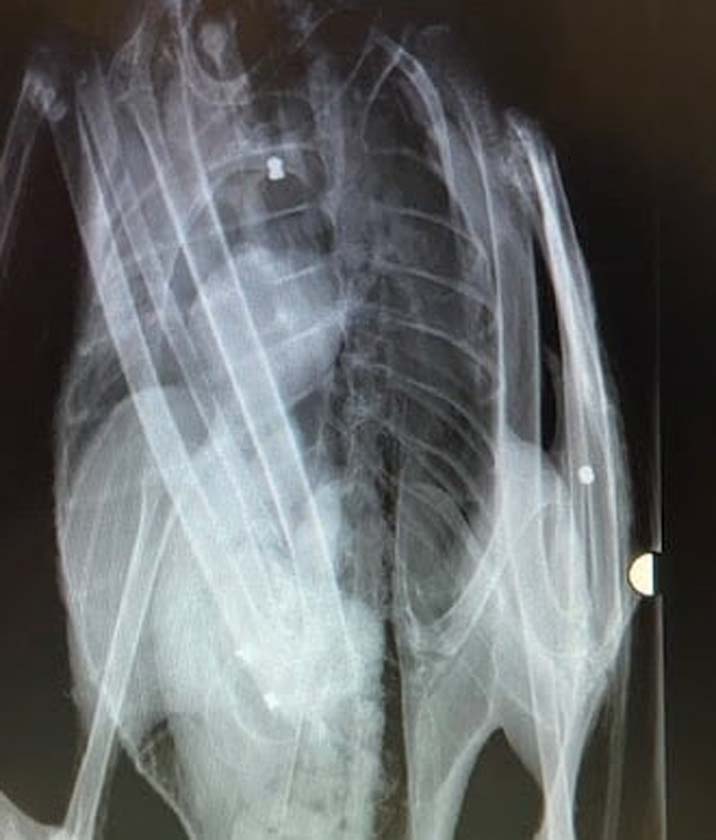

Reports included a hedgehog stoned to death, a dove shot with a crossbow, foxes trapped and then hunted by dogs and a swan shot six times.